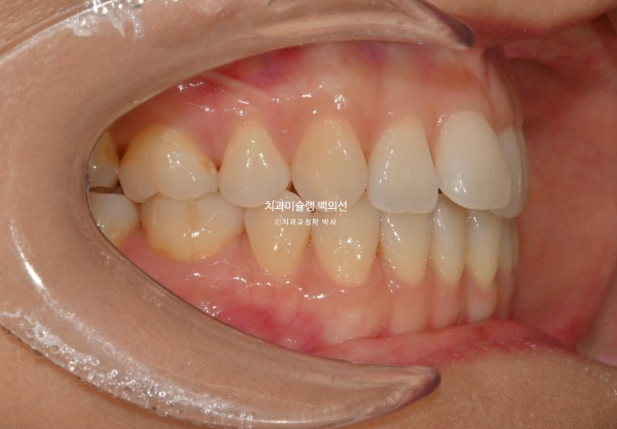

이제 전 후 비교 보겠습니다.

25.03~25.09

깔끔해진 미소가 돋보입니다.